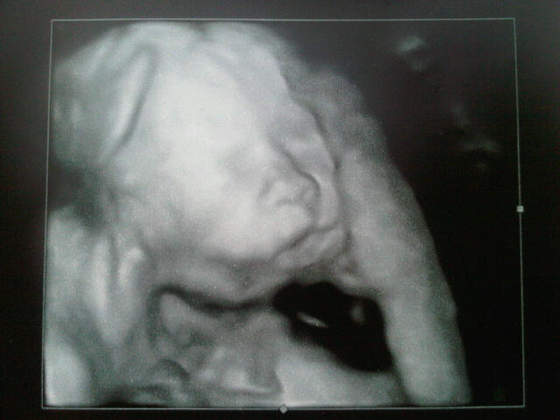

Zobacz załącznik 423947Zobacz załącznik 423948

Na piewszym pepowina wciela sie w kadr, a na drugim dzidzius nad czyms mysli ostro ;-)

Tak się złośliwiec ustawia, że buzię za każdym razem odwraca albo zasłania rączkami, za to siusiaka zawsze wystawi